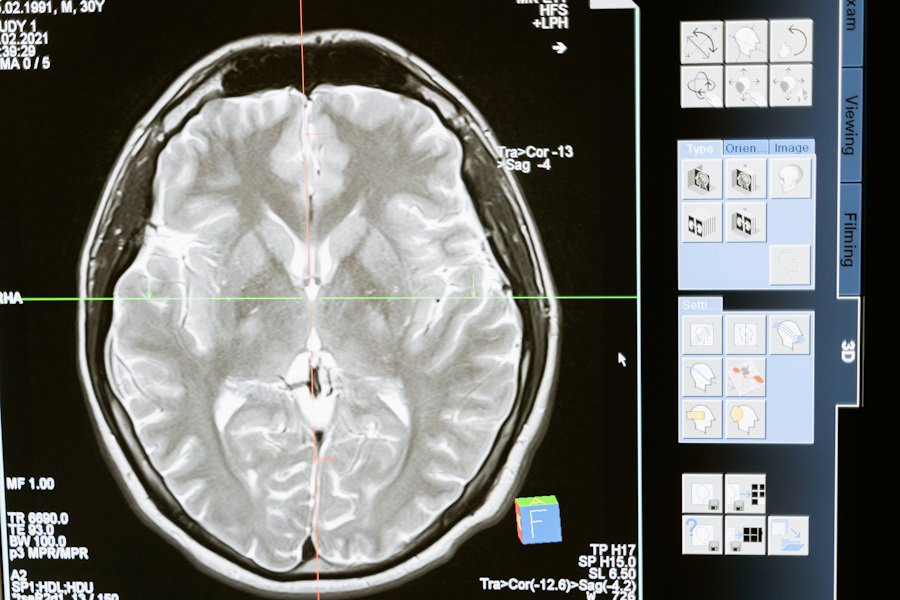

Фото из открытых источников

В исследовании психологов University of North Carolina была протестирована новая замкнутая система для измерения и стимулирования электрических паттернов мозга у пациентов с тяжелым депрессивным расстройством. Результаты показали значительное улучшение симптомов у большинства участников, сообщает Medical Xpress.